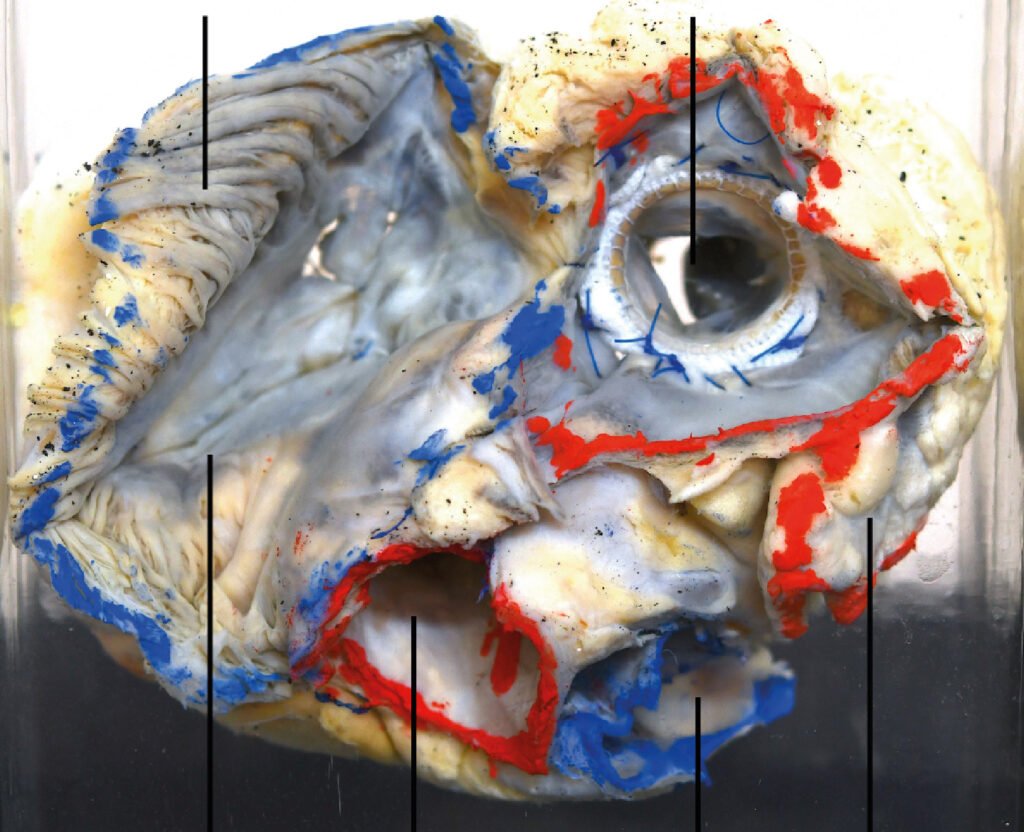

Museo.

Encontrarás los preparados de nuestro laboratorio en el museo de Anatomía J. J. Naón, Facultad de Medicina, Universidad de Buenos Aires, con su descripción.

Encontrarás los preparados de nuestro laboratorio en el museo de Anatomía J. J. Naón, Facultad de Medicina, Universidad de Buenos Aires, con su descripción.